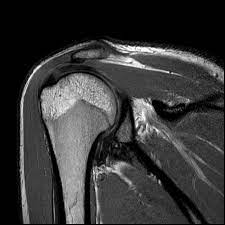

Enter the transformative power of Musculoskeletal MRI—a beacon of hope for individuals like Meera who find themselves trapped in a cycle of uncertainty and discomfort. Musculoskeletal MRI is a groundbreaking diagnostic tool that offers a detailed view of bones, joints, and soft tissues, enabling doctors to pinpoint the root cause of pain with remarkable accuracy.

The MRI results revealed a minor tear in Meera's meniscus, something that had been missed in previous X-rays and physical examinations. With this precise diagnosis in hand, her doctor was able to devise a targeted treatment plan, combining physiotherapy with medication, that set Meera on the path to recovery. Within weeks, she noticed a significant improvement in her mobility and a reduction in pain. The sense of liberation was profound—Meera was reclaiming her life, step by step.